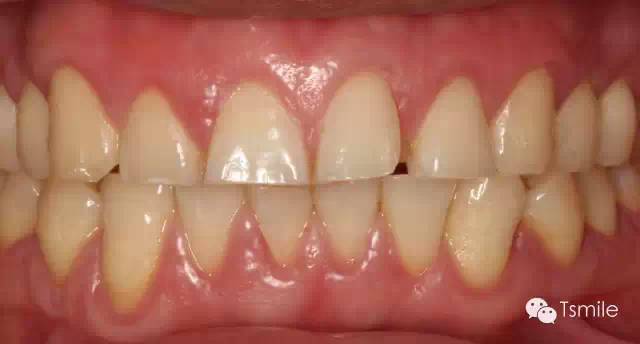

圖1: 夜磨牙導(dǎo)致的牙列重度磨耗

圖3 :夜磨牙導(dǎo)致的物理性磨耗

物理性的磨耗形成的磨耗面邊緣尖銳、表面光滑閃亮。而酸蝕癥導(dǎo)致的磨耗面邊緣圓鈍,多呈杯狀凹陷。

3.上下頜相對(duì)牙齒的磨耗量對(duì)比(amount)

物理性的磨耗上下頜相對(duì)牙齒牙面的磨耗量基本一致。而酸蝕癥導(dǎo)致的牙列重度磨耗上下頜相對(duì)牙齒牙面的磨耗量可以完全不同,甚至一側(cè)有嚴(yán)重的磨耗而對(duì)側(cè)完全沒有磨耗。

4. 上下頜相對(duì)牙齒的磨耗面是否有咬合接觸(contact)

物理性的磨耗所導(dǎo)致的牙列重度磨耗,其上下頜相對(duì)牙齒的磨耗面之間一定有咬合接觸。而化學(xué)性酸蝕癥所導(dǎo)致的牙列重度磨耗,其上下頜相對(duì)牙齒的磨耗面之間可能完全沒有咬合接觸。